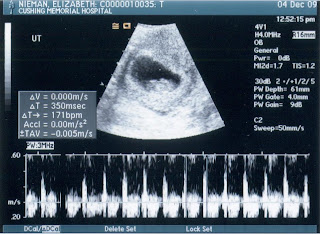

That black dot on the left in its head is its Stanford bound brain!

We got to see it bounce around my my belly and hear the amazing sound of its hearbeat. We created something that has a heart. That beats. Inside of my body. So crazy. So blessed.